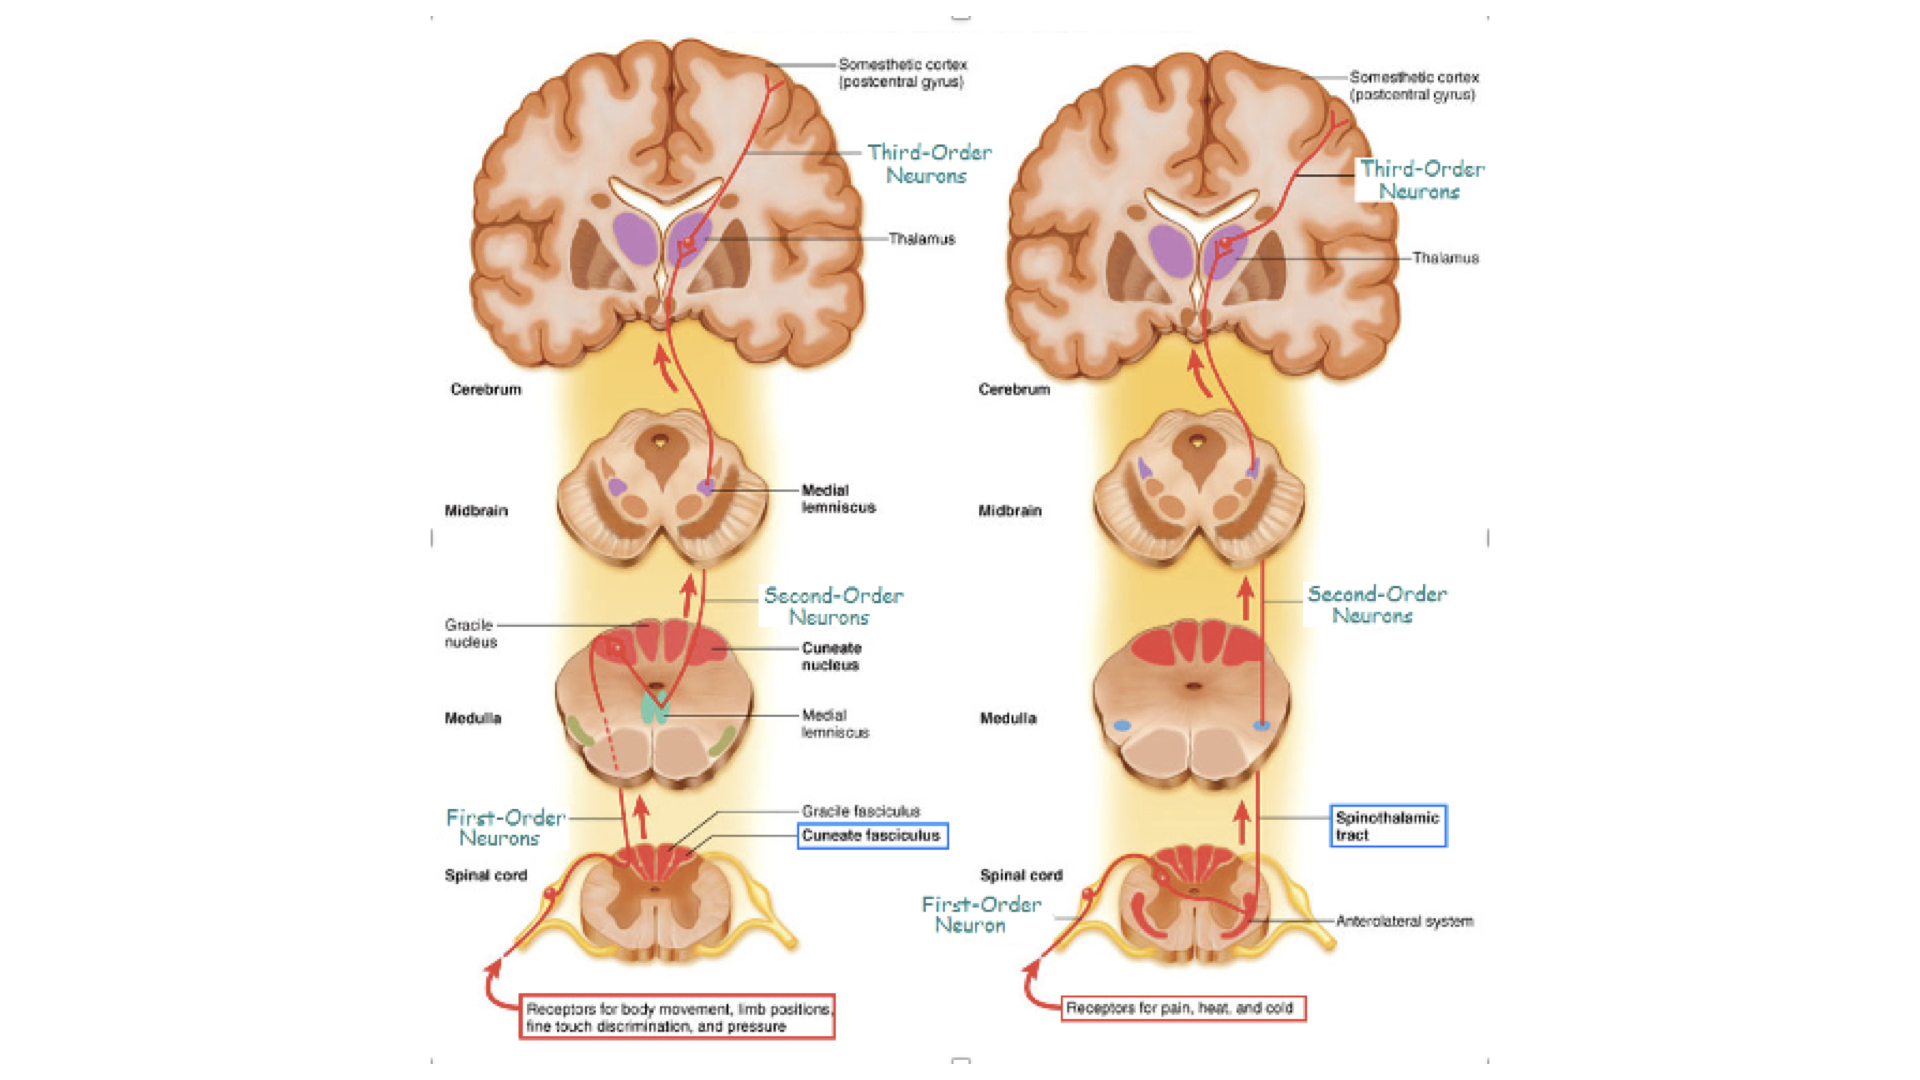

1. Ascending pathways have three neurons from sensor to cerebral cortex. Note that all go through the thalamus which serves as a filter.

Ascending Pathways

Ascending Pathways

f. Decussation simply means the cross over between right and left. Remember that sensory data from right side of body and motor responses to the right side of the body involve the left cerebral hemisphere. Sensory and motor data from and to the left side of the body involve the right cerebral hemisphere.